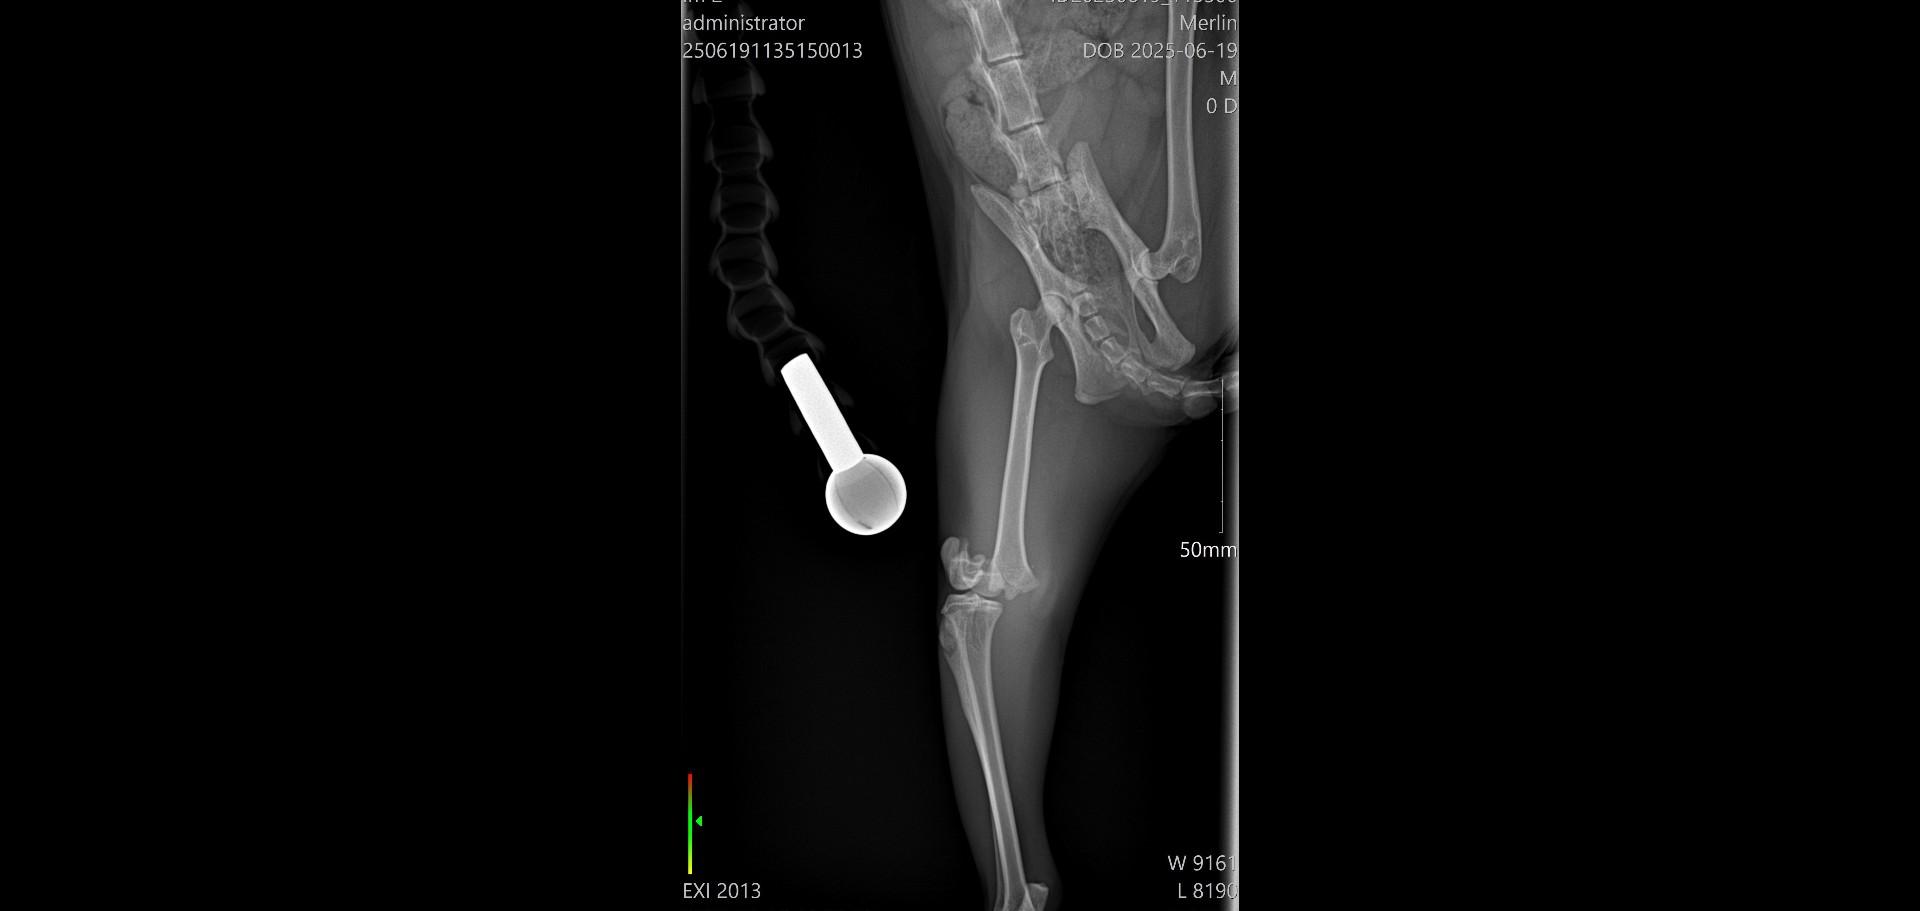

Dnes ráno měl  být Merlinek propuštěn do domácího léčení, bohužel jeho stav po narkóze neodpovídal běžnému stavu a musel ještě zůstat na klinice. Zítra budeme vědět víc a doufáme, že bude už v pořádku a pojede s námi domů, kde má vše připraveno na doléčení. Přikládáme snímky z rentgenu operované nožky. Děkujeme všem za podporu a pomoc s úhradu nákladů na operaci a hospitalizaci, které budou vysoké, bez vaší pomoci bychom to nezvládli.